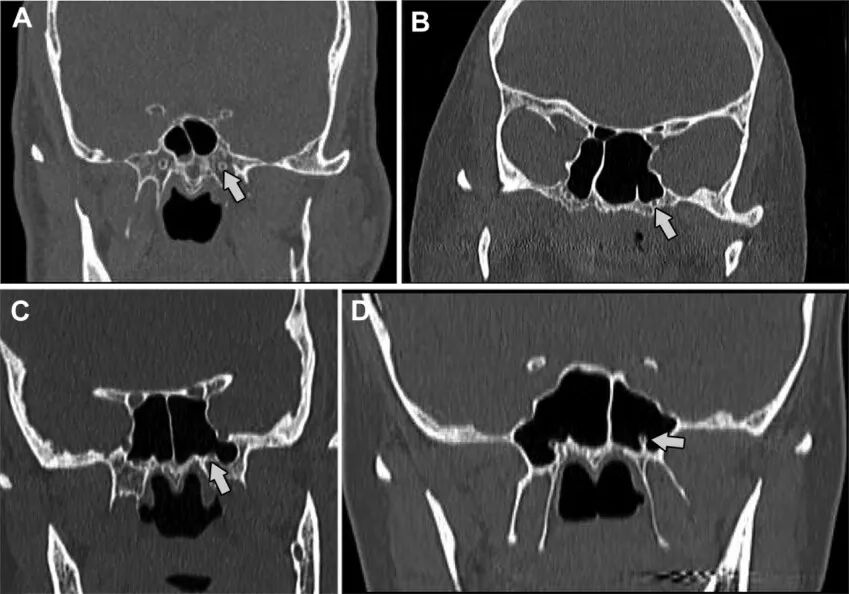

图1. 翼管的气化程度分型,A、B、C、D分别0、I、Ⅱ、Ⅲ型。箭头所指为翼管,翼管从完全被蝶骨围绕至完全被空气围绕。